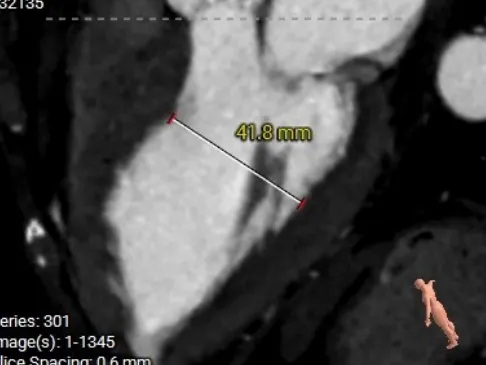

术前CT测量

主动脉根部测量

Annulus 26.2mm

LVOT 26.4mm

钙化积分:1371

SOV

22.6*34.9mm

STJ 31mm

AAO 34.8mm

-

Type0二叶瓣

流出道直筒型

左窦团块状重度钙化,右窦零星钙化

瓣上结构测量

瓣下2mm

26.3mm

瓣上2mm

23.9mm

瓣上4mm

23.3mm

瓣上6mm

22.1mm

瓣上8mm

22.2mm

瓣上10mm

冠脉风险评估

LCA Height

RCA Height

冠脉开口高度可,结合二叶瓣形态,预估冠脉风险相对较低。

左室测量

左室内径可,心室壁增厚。